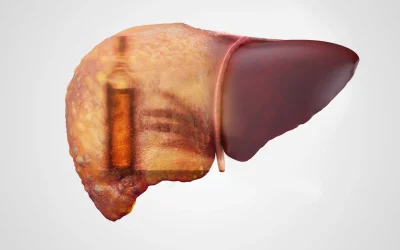

1. تأثیر بر کبد

کبد وظیفه تجزیه الکل را بر عهده دارد، اما مصرف زیاد الکل میتواند منجر به بیماریهای کبدی مانند کبد چرب، التهاب کبد و سیروز شود.

تخریب کبد باعث کاهش توانایی بدن در سمزدایی و تنظیم هورمونها میشود.